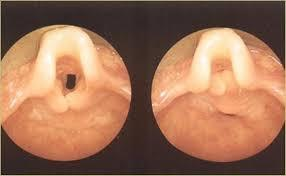

Post-Nasal Surgery Complication

A 40-year-old male post-nasal surgery with a whistling sound, crusting and epistaxis in the nose. Anterior rhinoscopy is shown.

Diagnosis

- Septal Perforation.

Common Cause

- Itโs a complication of Septoplasty due to surgical trauma or pricking.

Treatment

- No treatment

- Nasal wash

- Surgical repair

- Insertion of silicon โbuttonโ